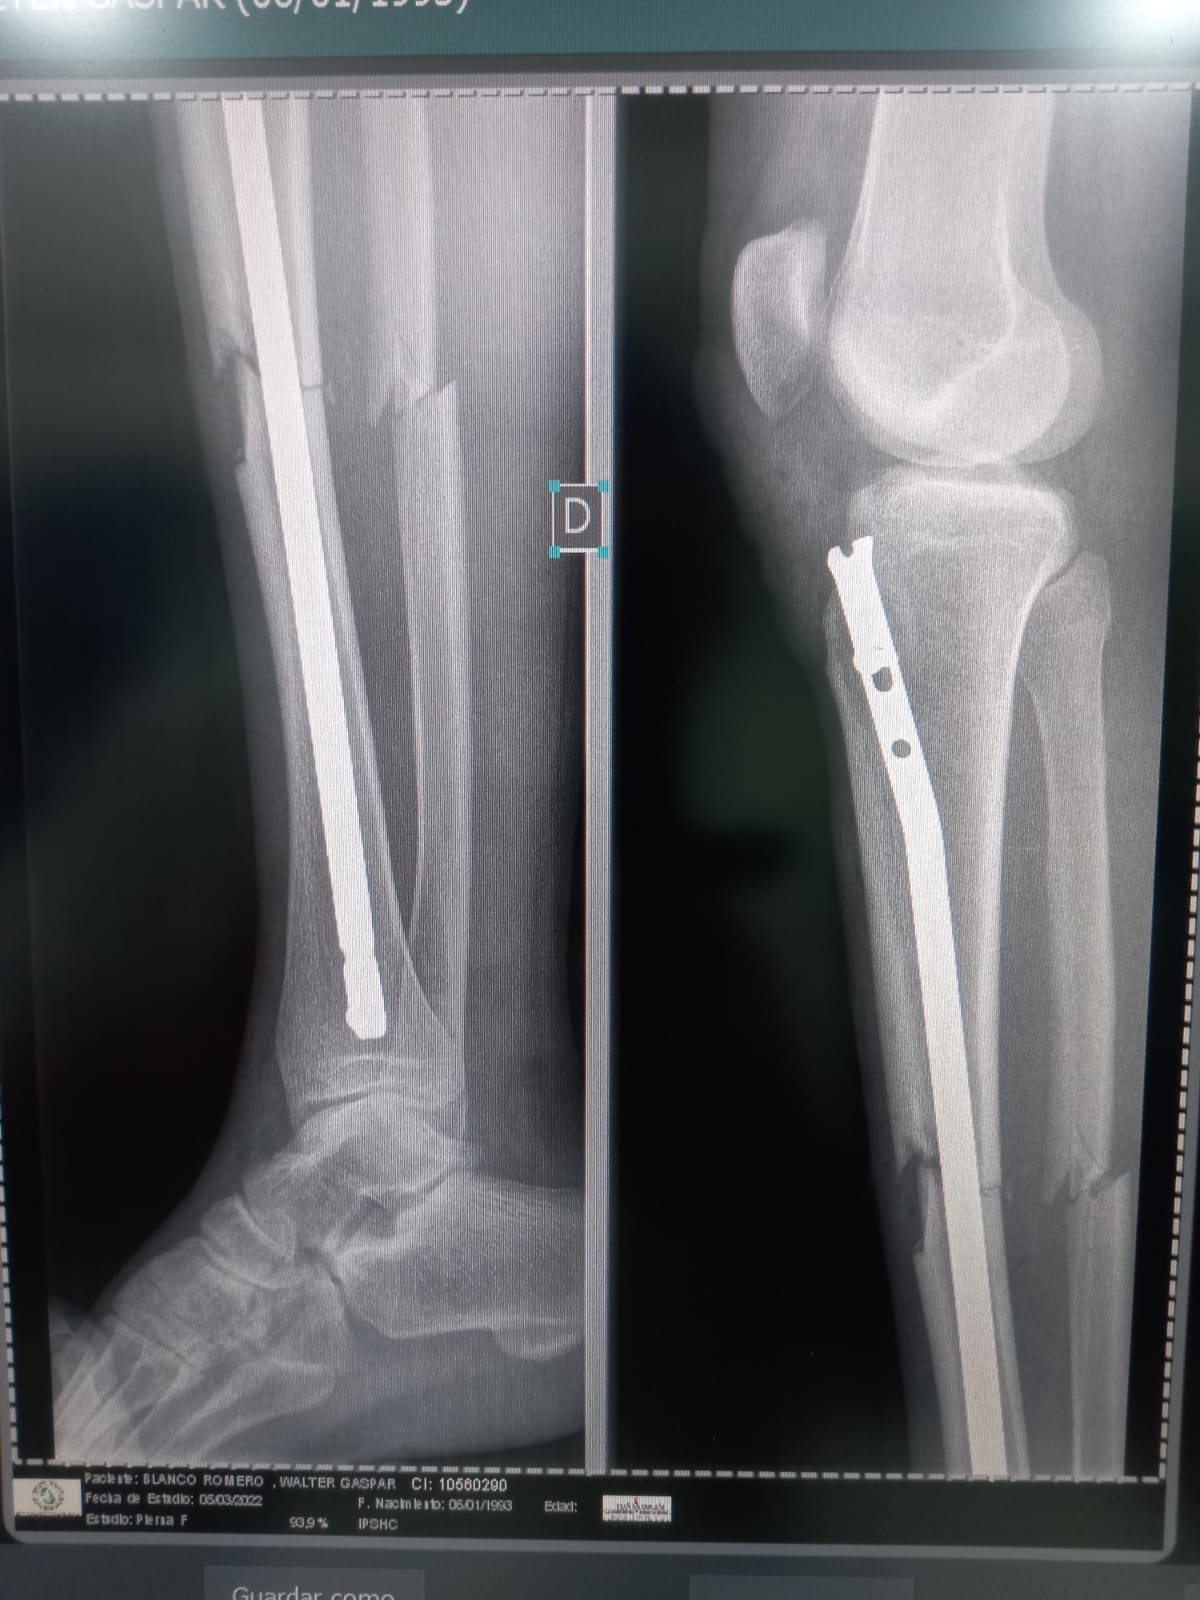

Walter tuvo un accidente laboral en motocicleta.

Lastimosamente se fracturó la tibia y el peroné.

Lo último que nos dijeron es que El Peroné esta con desplazamiento y posiblemente se vuelva a operar 😔